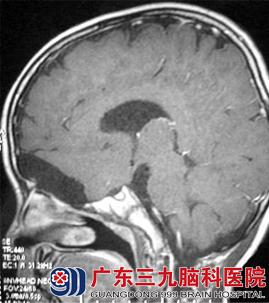

图6 T1WI矢状位增强:病变及其前方囊性部分未见强化

CT表现(图1、2):前颅窝底可见一等密度(与脑实质密度相同)占位性病变,其前方可见囊性的低密度影,与脑脊液密度相似,相邻脑组织受推压,未见明显水肿密度影。MR表现(图3-6):病变呈等T1等T2信号,边界清晰;其前方可见长T1长T2信号影,增强后,病变未见强化。弥散加权成像(DWI):未见病变弥散受限,前方囊性部分呈低信号。考虑为前颅窝脑外占位性病变。